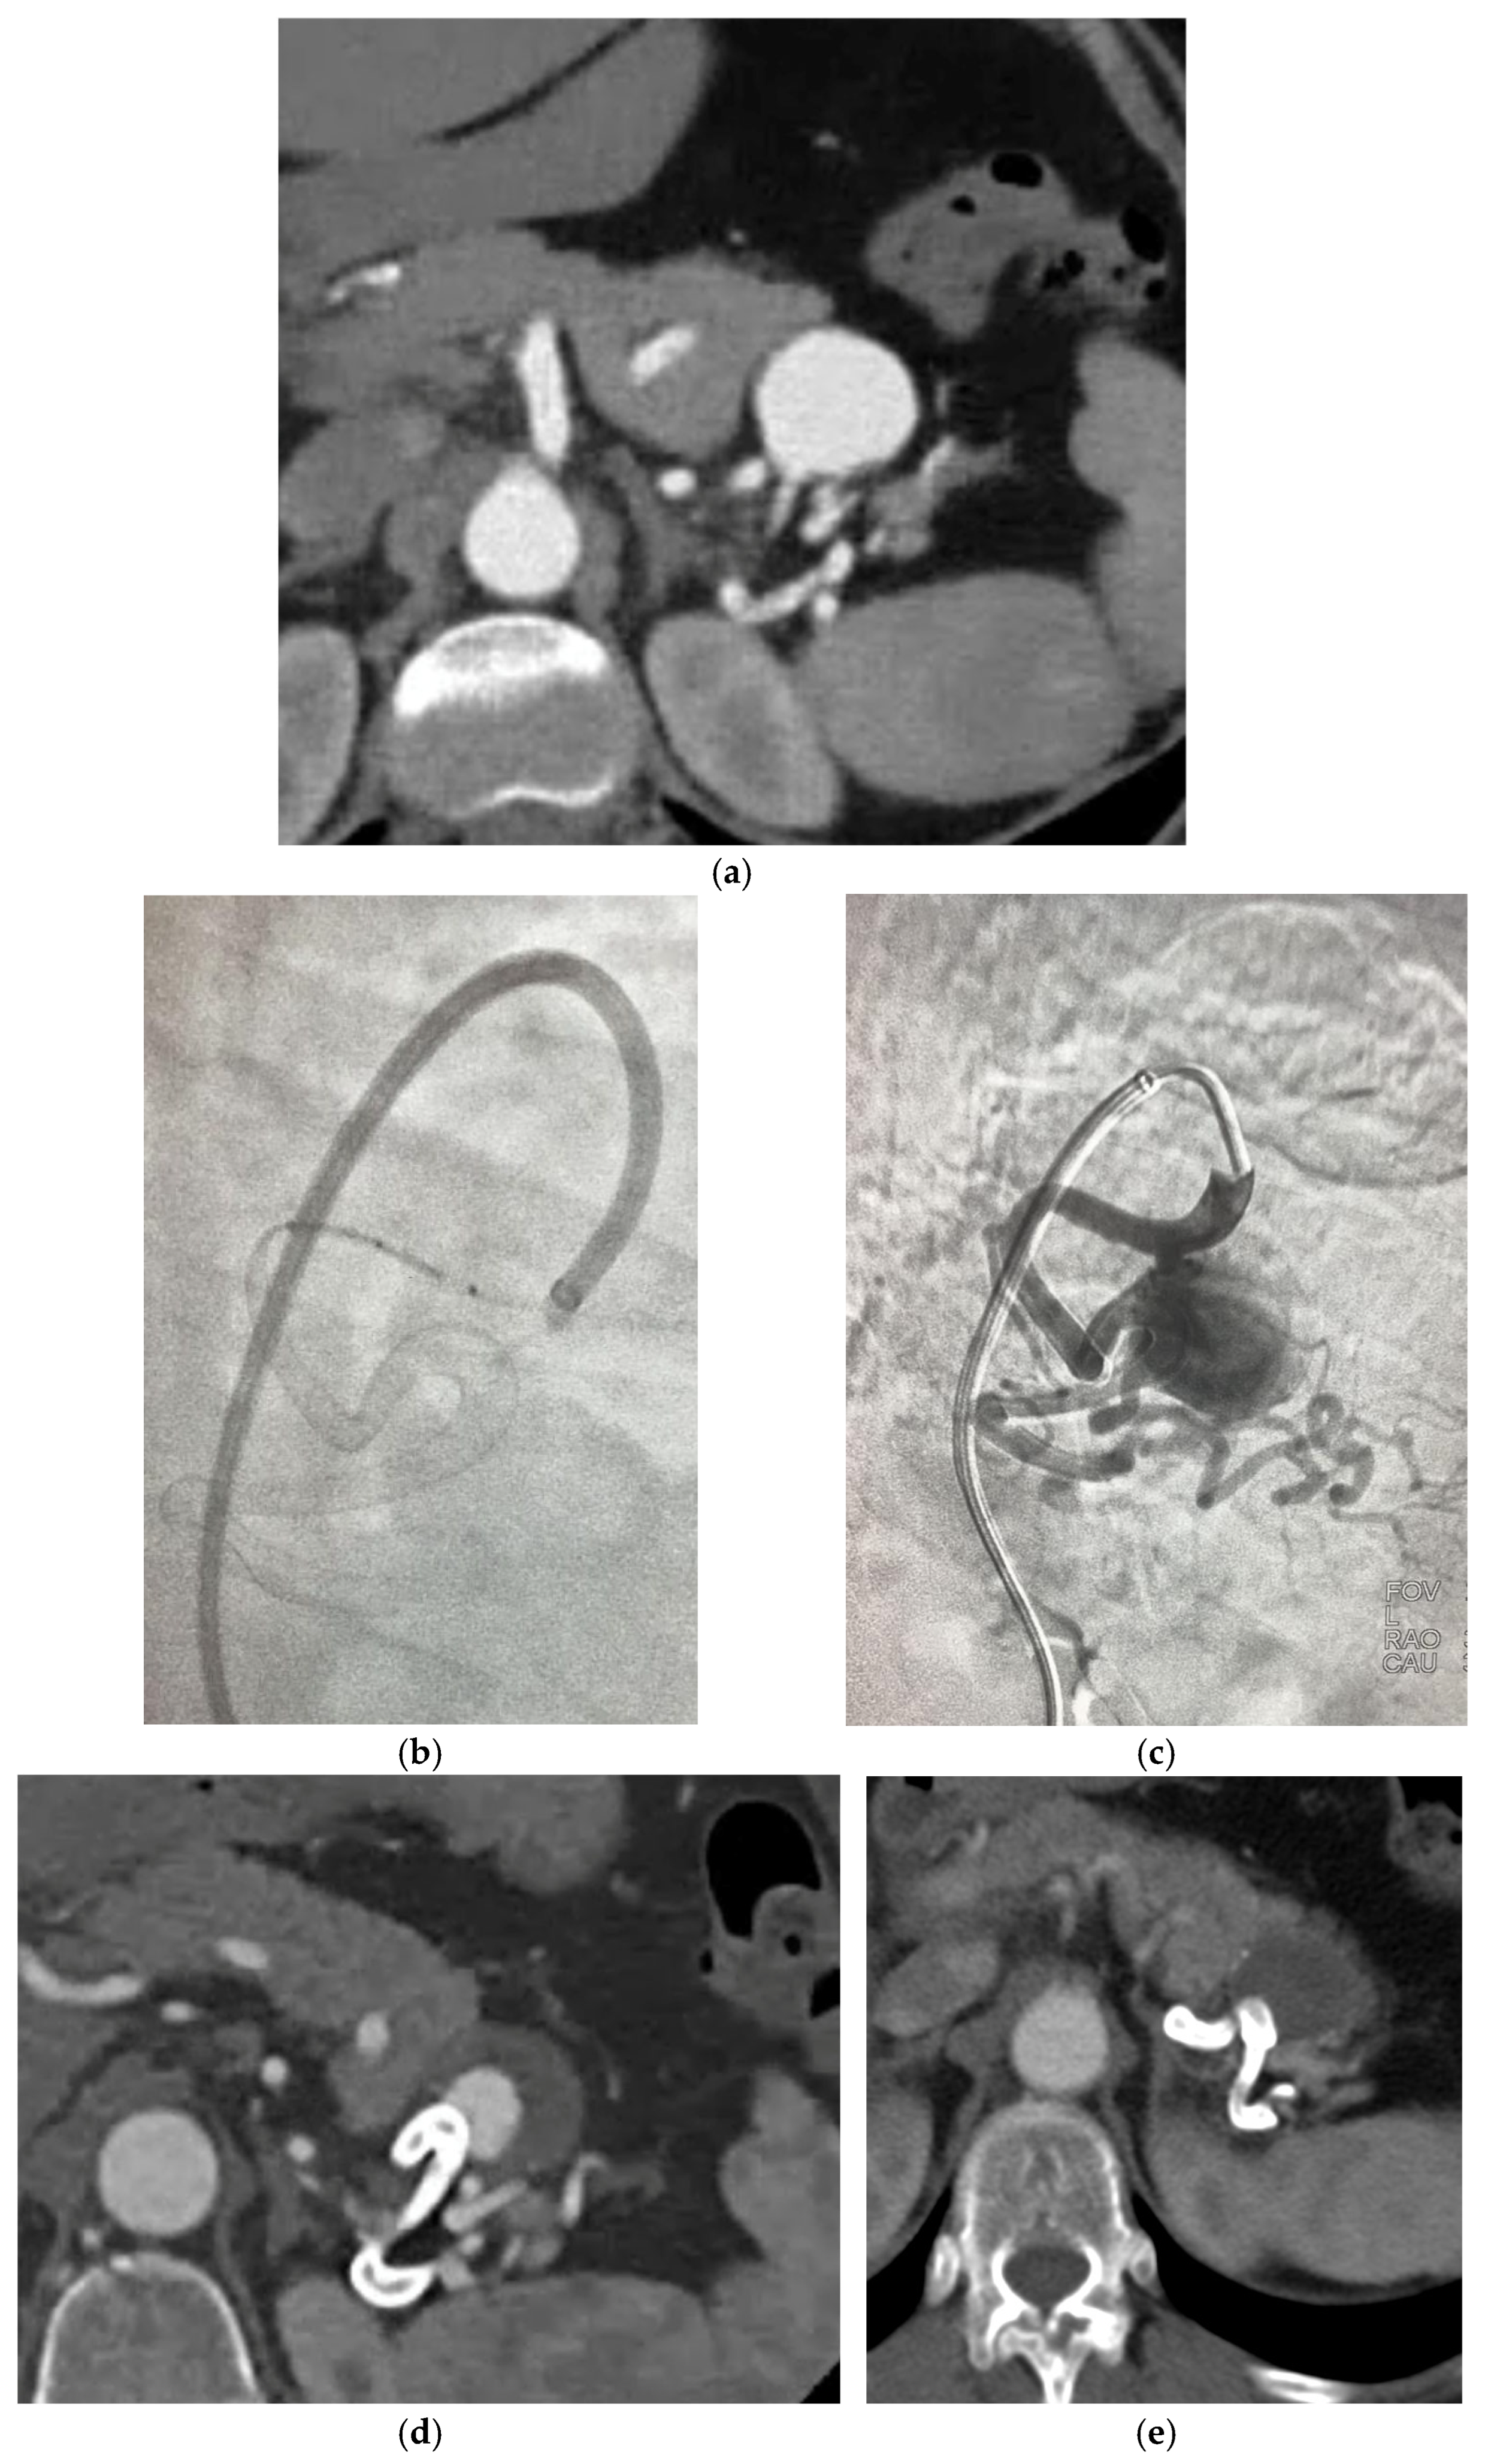

The new generation FDS have been associated with the highest rate of treatment efficacy (93.75%) compared to the other groups, however, despite the highest rate of intraprocedural complications (31.25%) and lowest technical success rates (75%). The cases reported having technical difficulties were due to prolapse of the stent in the aneurysm sac or to vessel dissection, 12% of which required re-intervention [18,23]. Intraprocedural issues were not seen in MOUS technique, only 1 case was observed in the use of double layer braided mesh stent which required reintervention with an additional stent positioning due to persistency of the aneurysm at 12 months CT angiogram [32] and only 1 in OGFDS Cardiatis [39], possibly due to the longer experience of doctors with these devices compared to the newer ones. The high rate of technical complications associated with the use of NGFDS can be partly explained by their predominant use in particularly complex cases, where they often represent the only available therapeutic option. This is especially true for tortuous and distal locations, where other techniques are not applicable. However, not all the articles analysed the exact location of the aneurysm, hence we could not clearly highlight this aspect, thus limiting our ability to directly correlate technical complications to the specific anatomical location of the treated aneurysms. Another issue regarding NGFDS, is the size available to date that limit their use in vessel with a dimeter > 7 mm. Figure 6a–e describe a case of NGFDS from our institution.

Figure 6. (a) Angio—CT shows 4-cm splenic distal artery aneurysm with three efferent vessels. (b,c) DSA showing the placement of a FD Derivo 6 × 5 cm. (d,e) Angio CT of 1 and 6 months FU with partial and total thrombosis of the sac. Patency of efferent vessels.